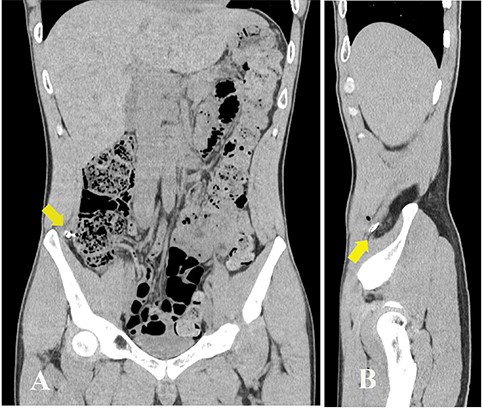

A 27-year-old man working in a forging factory presented to our hospital with acute abdominal pain. He reported that, 3 hours before presentation, a metal fragment came flying from the operating power hammer, which molded molten metal into the desired shape by striking it. Although he was wearing protective clothing, the fragment penetrated through it and caused sharp pain. Physical examination revealed a 1 cm wound, resembling a stab wound above the right iliac crest (Fig. 1A). The patient experienced localized abdominal pain around the wound; however, there were no signs of peritoneal irritation. His vital signs were stable and laboratory data showed no abnormalities except for a slightly increased C-reactive protein level of 0.91 mg/dL (reference range, 0–0.14). A spine abdominal radiograph showed a 1 cm-sized radiopaque object in the lower right abdomen (Fig. 1B). An abdominal computed tomography revealed a radiopaque object near the peritoneum; however, its exact location being extraperitoneal or intraperitoneal could not be determined (Fig. 2A and B). The abdominal cavity did not have free air or fluid retention. The patient was diagnosed to have a foreign body near the peritoneum and surgical removal was planned. The operation was performed using single-incision plus one-port laparoscopic surgery (SILS plus one). A 1.5 cm longitudinal incision was made at the umbilicus to access the abdominal cavity, after which the wound retractor (Smart Retractor XS; TOP Corp., Tokyo, Japan) was inserted. It was mounted to a single-port access device (Free Access; TOP Corp., Tokyo, Japan). Subsequently a 5-mm trocar was placed just above the pubic symphysis. Laparoscopic inspection following pneumoperitoneum revealed no damage to the peritoneum or internal organs (Fig. 3A). Although we assumed the foreign body was located in the abdominal wall, laparoscopic inspection could not confirm its position. Real-time fluoroscopy was used to locate the fragment. The nearest peritoneum was incised and the abdominal muscle was dissected until the foreign body was observed (Fig. 3B). It was found embedded in the transversus abdominis muscle (Fig. 3C) and was safely removed using forceps (Fig. 3D). The object was 1.5 cm long and sharp at both ends (Fig. 4). The patient was discharged from our hospital after a good postoperative course.

Abdominal CT showing a radiopaque object near the peritoneum. (A) coronal view; (B) sagittal view (arrows).